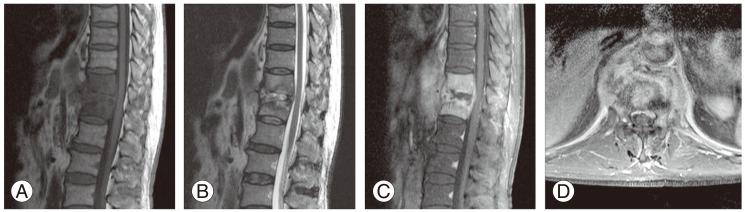

Comparison of pyogenic spondylitis and tuberculous spondylitis.

Pyogenic spondylitis and tuberculous spondylitis are common causes of spinal infection. It is difficult to differentiate tuberculous spondylitis and pyogenic spondylitis clinically and radiologically. Recently magnetic resonance imaging has been reported to be beneficial for early diagnosis and differential diagnosis of the spondylitis, and is being used extensively for diagnosis. However, the diagnosis must be considered in combination with corresponding changes in clinical manifestations, radiological findings, blood and tissue cultures and histopathological findings. Conservative treatments, including antimicrobial medications, are started initially. Surgical treatments, which include anterior or posterior approach, single-stage or two-stage surgery, with or without instrumentation, may be performed as indicated.